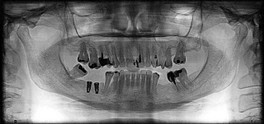

Empleo de los implantes dentales como recurso para la resolución funcional y estética ante la ausencia de piezas dentales.